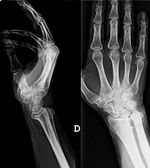

En la imagen de radiología convencional en proyecciones anteroposterior, y perfil de mano y muñeca objetivamos una artropatía degenerativa evolucionada con marcada desestructuración articular radio-cubital distal, con alargamiento y elevación del cúbito respecto al radio (cubito plus), y desviación dorsal de la cabeza cubital (fig. 2), probablemente debido a una secuela de una fractura radio distal antigua, no referenciada por el paciente, con acortamiento del radio y subluxación de la cabeza cubital.